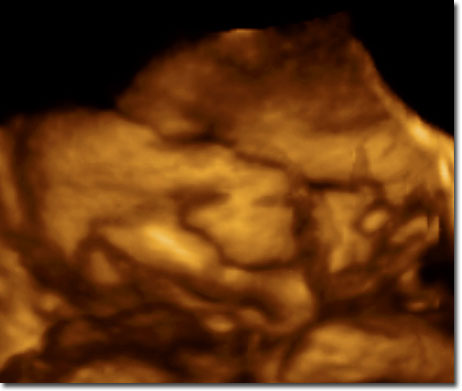

Faszination Live 3D/4D zurück zu Home

Live 3D/4D

Drillinge Live3D/4D

paradiesisch schön hier: 3D/4D live in der 30. SSW:

aber manchmal muss ich hier tief nachdenken: 3D/4D live in der 35. SSW: